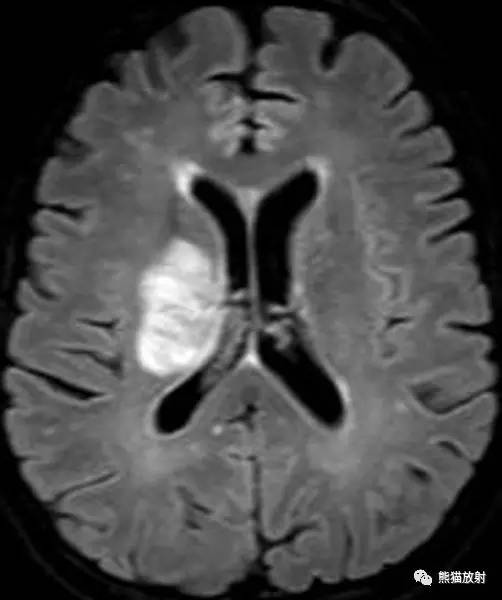

CASE 1

病史:47岁男性,最近诊断为HIV感染,CD4计数为50,精神状态异常。

图像:轴位FLAIR,冠状T1增强,DWI,ADC图。

MRI表现:FLAIR示双侧额叶白质高信号灶,胼胝体前部及外周弥散受限,无明显占位效应,增强扫描无强化。

诊断:经典进行性多灶性白质脑病